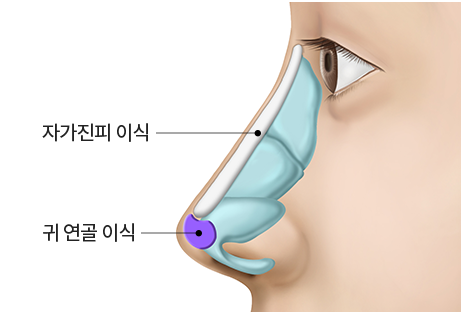

step 02. 귀 연골 채취

step 03. 자가진피와 연골 디자인

step 04. 콧대-진피, 코끝 연골 이식

코끝은 별도로 '귀연골이나 늑연골'이 사용됩니다. 이건 구조적인 이유 때문입니다.

코끝은 형태를 유지할 지지대 역할이 필요하고, 입을 움직일 때 마다 움직이기 때문에

콧대에 비해 코끝이 더 쉽게 벌어지거나 처지는 경향이 있기 때문입니다.

'귀연골이나 늑연골'을 사용하는 것이 코끝 모양을 디테일하게 살리면서

유지시켜주는 데 좋습니다.